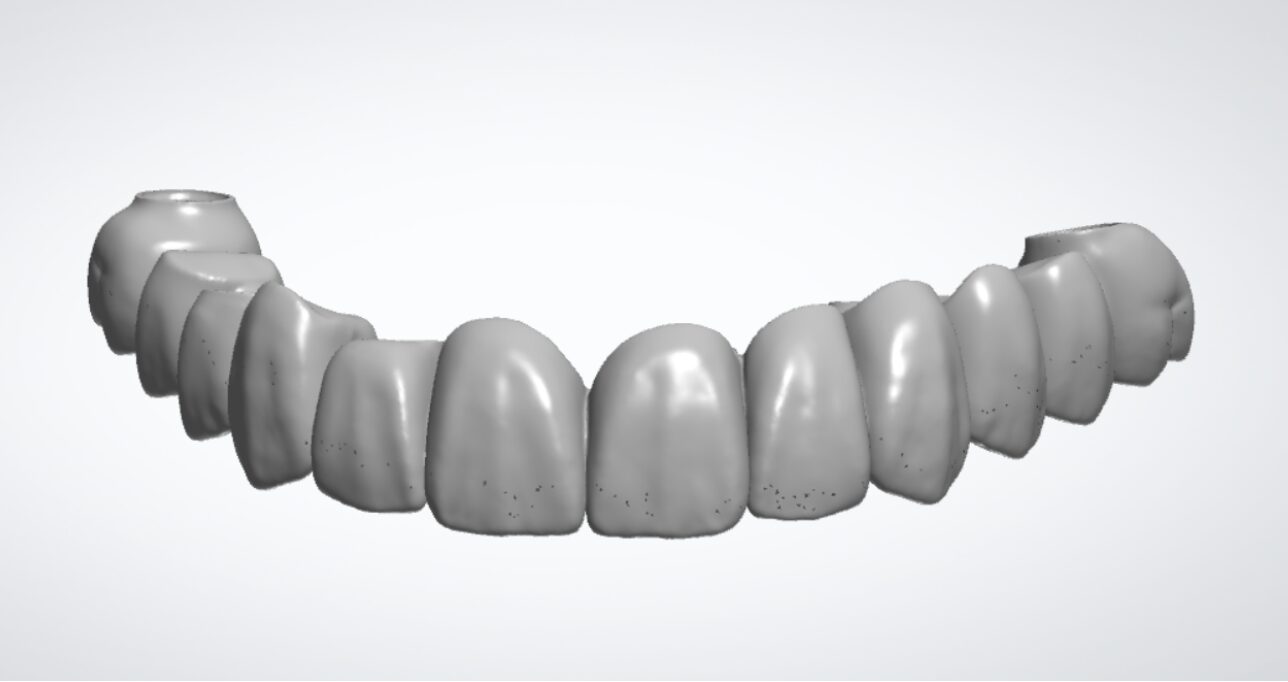

ステップ5:最終的な歯(セラミック冠)の製作

この固定式の仮歯には、最終的な歯を成功させるための重要な役割があります。しっかりと噛めるようになることで、噛む力(咬合力)が回復し、顎の動きや噛み合わせも微妙に変化します。 この仮歯を数ヶ月間使用していただきながら、発音や見た目、清掃性、噛み心地などを細かく微調整し、患者さんにとって最適な状態を探っていきます。 この情報を基に、最終的な「セラミック冠(上部構造)」を精密に製作します。

今回の治療では、インプラントの埋入位置のシミュレーションから、最終的な歯の設計・製作に至るまで、デジタル機器(口腔内スキャナーやCAD/CAMシステムなど)を駆使して行いました。 これにより、精度の高い治療と、機能的かつ審美的な仕上がりを両立が期待できます。

歯の形を決めるために行う口の中の型取りは、短時間で不快感が少なくなるよう、従来のゴム状の素材を口に入れる方法ではなく、口腔内スキャナーを使用したデジタルシステムを活用しています。